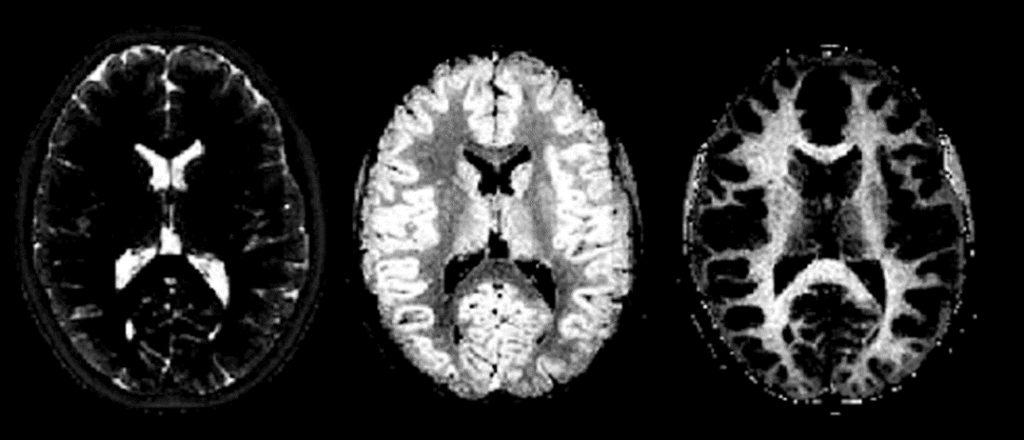

Il progetto “The Fingerprinting of Inherited leukoencephalopathies: A new Brain imaging, genetic and clinical Assessment (FIABA)” si propone di studiare le malattie della sostanza bianca del cervello in età pediatrica con tecniche avanzate di risonanza magnetica quantitativa a campo alto (3T) e ultra-alto (7T).

Per ridurre i lunghi tempi di scansione e la sensibilità al movimento del paziente che limitano l’efficacia della RM è stato proposto un metodo chiamato MR Fingerprinting (MRF). Questo consente di produrre mappe quantitative tridimensionali, presenta una ridotta sensibilità al movimento e può essere utilizzata per acquisire un esame anatomico in circa cinque minuti a una risoluzione spaziale standard. Tuttavia, l’efficacia della MRF nella pratica clinica non è ancora stata dimostrata. Questo studio si propone di valutarla nell’esecuzione di esami diagnostici in pazienti adulti e pediatrici.